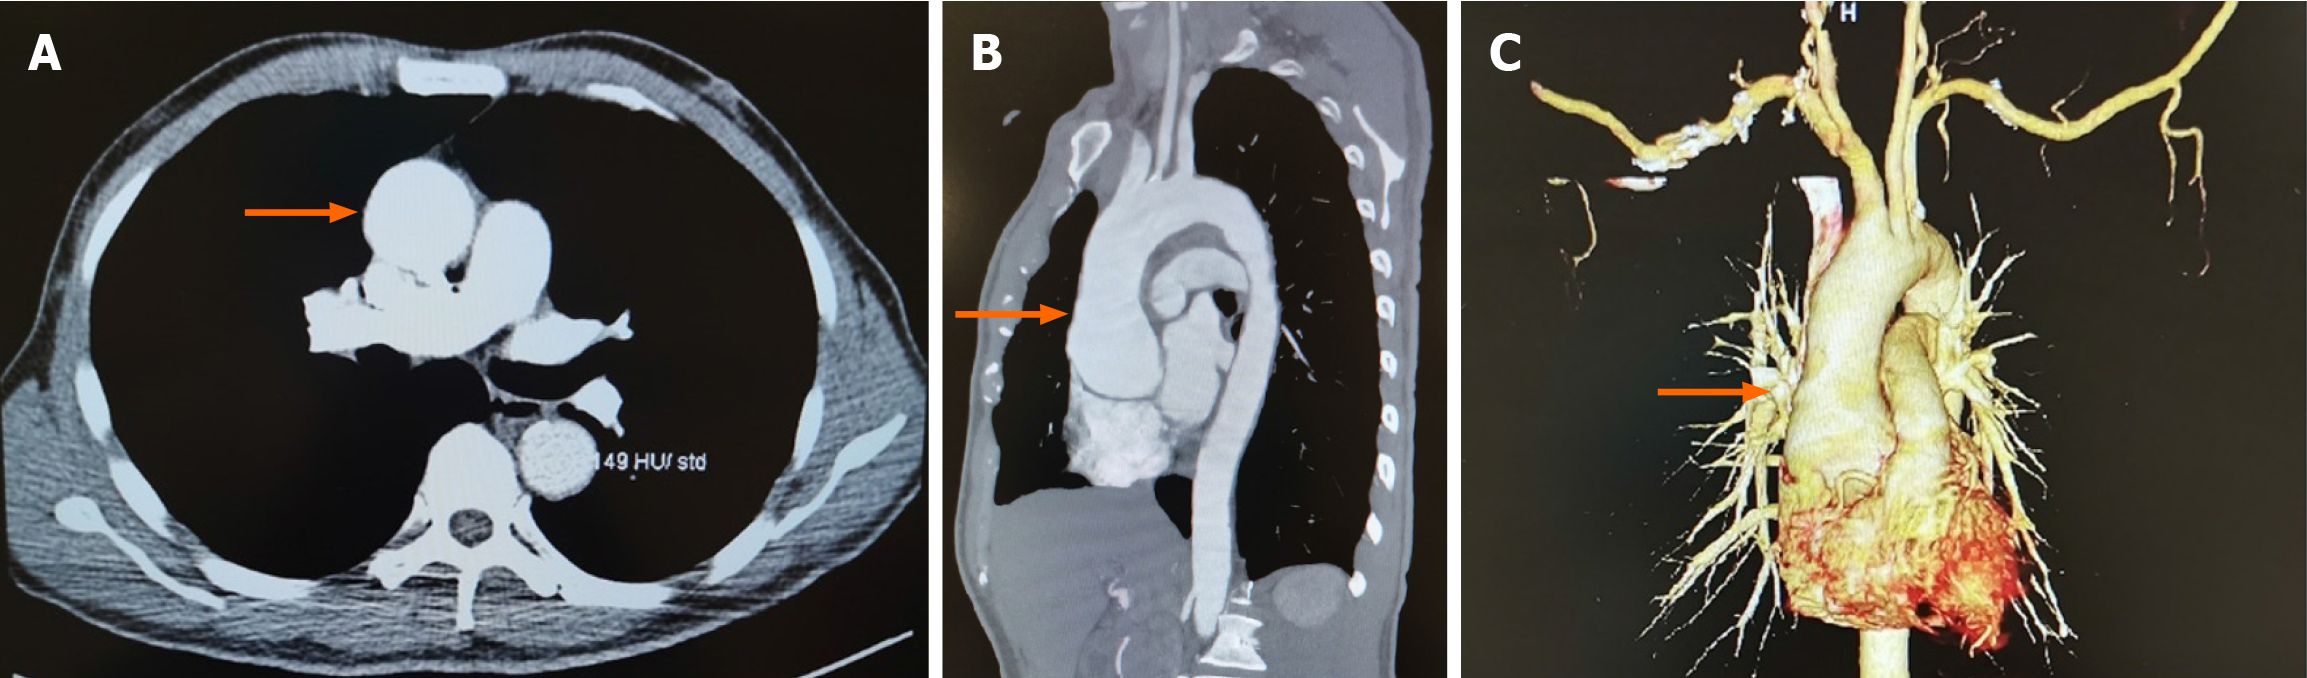

Computed tomography angiography demonstrated aortic root aneurysmal dilatation (maximum cross-sectional area of approximately 6.2 cm × 5.7 cm) (Figure 1).

The patient was scheduled to undergo a Bentall procedure. Extracorporeal circulation was established via aortic and bicaval cannulation after chest opening. After aortic clamping, cardiac arrest was induced using cold cardioplegia administered via right and left coronary ostium. The cardioplegia solution consisted of a high-potassium formulation with added magnesium and lidocaine to enhance myocardial protection. The aorta was trimmed to the proximal to the opening of the innominate artery. The ostia of the left and right coronary arteries were isolated and trimmed into a button shape, the aortic valve leaflets were removed, and an artificial blood vessel with a valve was placed and sutured. Following aortic cross-clamp release, the patient resumed sinus rhythm and was successfully weaned off CPB. Transoesophageal echocardiography (TEE) showed normally functioning prosthetic aortic valve, mild mitral regurgitation, mild tricuspid regurgitation, and a patent blood stream in the ostia of the left and right coronary artery. Five minutes later, the patient suddenly developed episodes of VF. CPB was initiated again, and the patient was immediately defibrillated to sinus rhythm. CPB was removed after achieving a relatively stable condition. The procedure was resumed uneventfully until sternum closing. However, the patient developed VF again and cardiac arrest followed. Spontaneous circulation was restored after 10 minutes through external defibrillation, cardiopulmonary resuscitation (CPR), administration of epinephrine and lidocaine, and hypothermic cerebral protection. At this point, TEE demonstrated the absence of significant bubbles within both the atrial and ventricular chambers, normal functioning of prosthetic valves, and uncoordinated as well as weak myocardial contraction. Arterial blood gas analysis indicated pH 7.296, PCO2 42.3 mmHg, PO2 278.9 mmHg, K+ 3.35 mmol/L, Ca2+ 1.054 mmol/L, total hemoglobin concentrations 137.7 g/L, lactate 3.6 mmol/L, and base excess -6.04. Potassium and calcium were supplemented to ameliorate the internal environment, and a continuous transfusion of epinephrine and noradrenaline was administered to increase myocardial contractility and cardiac afterload, improve cardiac function, and maintain stable circulation. Meanwhile, cardiac surgeons reopened the chest for further exploration to identify the underlying causes of VF. Because VF recurred during sternum closure, suggesting a possible mechanical or ischemic trigger related to chest closure. However, no mechanical obstruction of the coronary artery was detected, and intra-coronary artery air embolus was ruled out based on continuous TEE monitoring results. After determining that the patient's vital signs were stable, the surgeons closed the sternum again. But an electrical storm of ventricular fibrillation recurred, which was not reversed by external direct current shocks. Sudden cardiac arrested ensued once more and CPR was administered. The chest was re-opened for internal defibrillation. Subsequently, CPB was promptly established. Immediate TEE results demonstrated absence of significant bubbles in the atrial and ventricular chambers, no myocardial edema, but weak myocardial contractility with regional wall motion abnormalities (Video). An ECG showed ST-segment elevation (Figure 2). Additionally, at the moment of sternum closing, arterial blood gas analysis revealed normal parameters. Considering the ECG, TEE results, operation way, and the timing of VF episodes, cardiologists and cardiac surgeons concluded that coronary insufficiency was the most likely cause of episodes of repeated VF in this patient. Therefore, CABG (proximal right coronary artery and the left anterior descending artery) was determined as the next step of treatment.